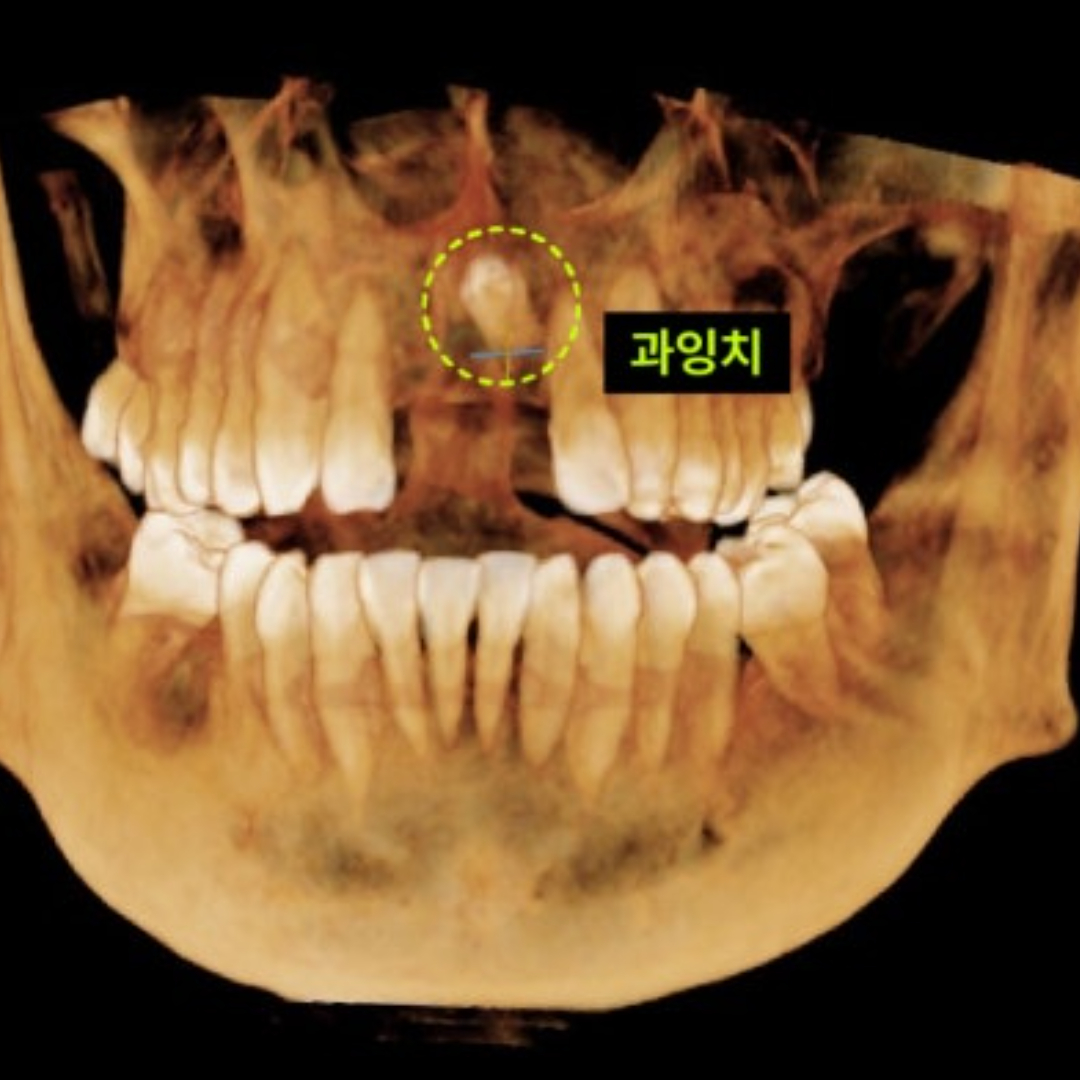

- 상악동 수술

- 부족한 잇몸뼈도 문제없다: 정교한 상악동 임플란트

- 임플란트

- 상악동거상술, 고난이도 임플란트치료 증례

- 브릿지를 임플란트로/발치와 동시에 상악동 수술, 임플란트